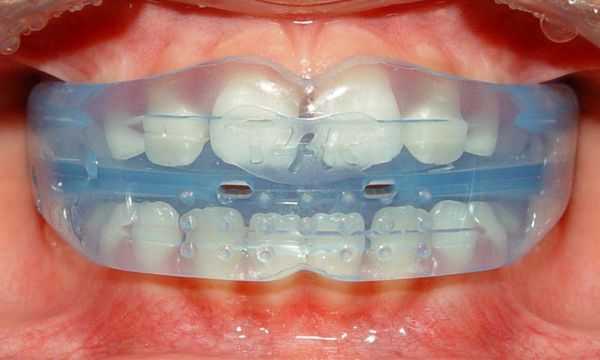

Для исправления прикуса используют съёмные и несъёмные ортодонтические пластинки из пластмассы с различными видами крепления (кламмеры, минивинты, ортодонтические кольца и коронки), а также другие конструкции с активными элементами (винтами и пружинами). Такие аппараты могут быть одночелюстными, двучелюстными и одночелюстными с межчелюстным действием.

Самая распространённая ортодонтическая аппаратура для исправления прикуса — брекет-системы. Для этого используются различные дополнительные приспособления: кнопки и крючки, эластики и эластичные цепочки.

Срок лечения брекет-системами в среднем составляет 15-18 месяцев и проводится в обязательном порядке на двух челюстях с последующим ношением ретейнера (шины) не менее 1,5 сроков активного периода лечения.

Сейчас большую популярность набирает лечение с помощью элайнеров — прозрачных капп с заложенной траекторией перемещения зубов. Этот метод, как и другие, имеет свои преимущества и недостатки. При грамотном планировании лечения и ответственном подходе пациента добиться ожидаемых результатов можно за 12-15 месяцев.